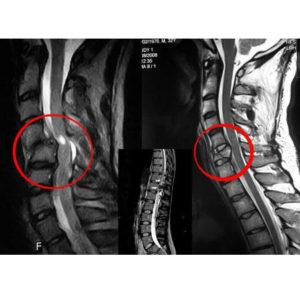

Как оценить состояние спинного мозга у человека после травмы? Для определения степени повреждения необходимо провести рентгенографию (желательно в двух проекциях).

Компьютерная и магнитно-резонансная томография предоставляют наиболее полное представление о состоянии позвоночника и спинного мозга. Эти методы позволяют визуализировать спинной мозг как в продольном, так и в поперечном сечении, а также обнаружить грыжи, осколки, кровоизлияния, повреждения нервных корешков и опухолевые образования.

Миелография используется для диагностики состояния нервных окончаний.